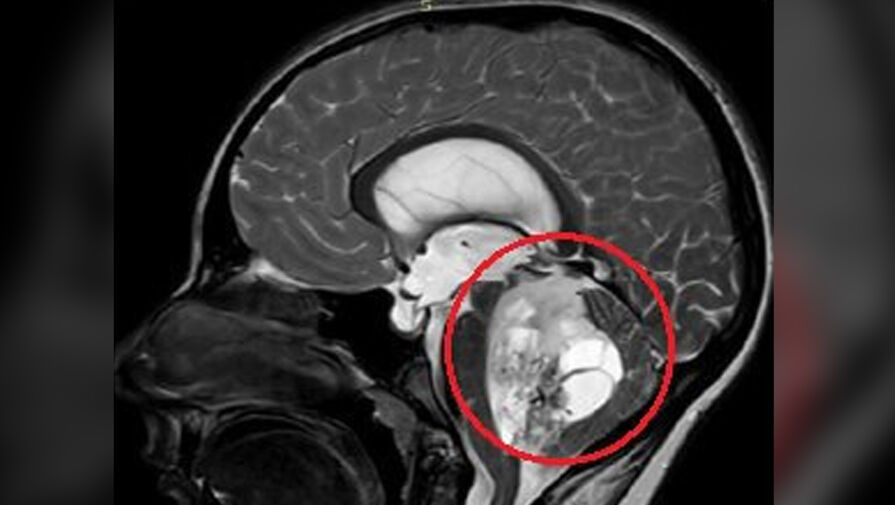

По словам медиков, юноша жаловался на постоянную тошноту и рвоту, которые не удавалось купировать консервативными методами. На обследовании специалисты обнаружили пятисантиметровую опухоль в задней черепной ямке. По словам врачей, ее дальнейший рост мог привести к нарушению жизненно важных функций мальчика.

«Сложность данного случая заключалась в том, что опухоль росла из области, которая отвечает за жизненно важные функции - любое, даже маленькое повреждение могли привести к тяжелым неврологическим осложнениям», — отметили нейрохирурги.